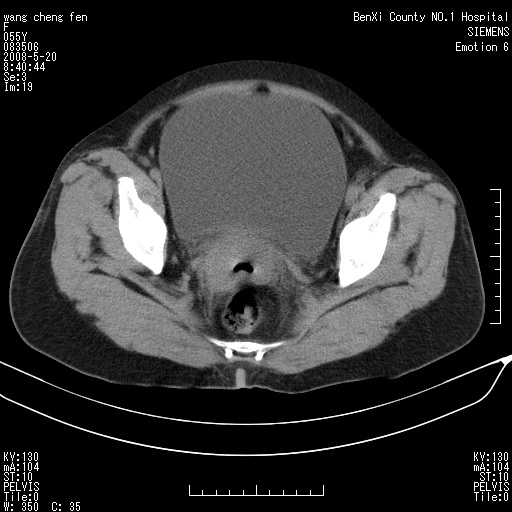

女、绝经后阴道流血3个月

左侧附件区可见一囊性占位,边缘清楚,内可见不规则形软组织影 ce:囊壁及内部可见强化 考虑 卵巢囊腺瘤

左侧附件区巨大囊实性病灶,边缘光整,病灶囊壁较厚,增强示囊壁及实性部分明显强化,强化呈度与宫体实质大致相同,宫腔积液征像,未见盆腔积液等其他异常,考虑左侧卵巢囊腺癌,不除外囊腺瘤及浆膜下肌瘤坏死

左侧附件区巨大囊实性病灶,边缘光整,病灶囊壁较厚,增强示囊壁及实性部分明显强化,强化呈度与宫体实质大致相同,宫腔积液征像,未见盆腔积液等其他异常。绝经后阴道流血3个月,结合病史左侧卵巢囊腺癌首先考虑,宫腔扩大不除外累及。期待结果。

支持浆膜下子宫肌瘤.之前由于网络原因未看全图片,现在重看,宫颈见一类圆形低密度影,增强轻度强化,低于肌层强化,宫腔扩大,考虑宫颈癌伴宫腔积液可能性大.